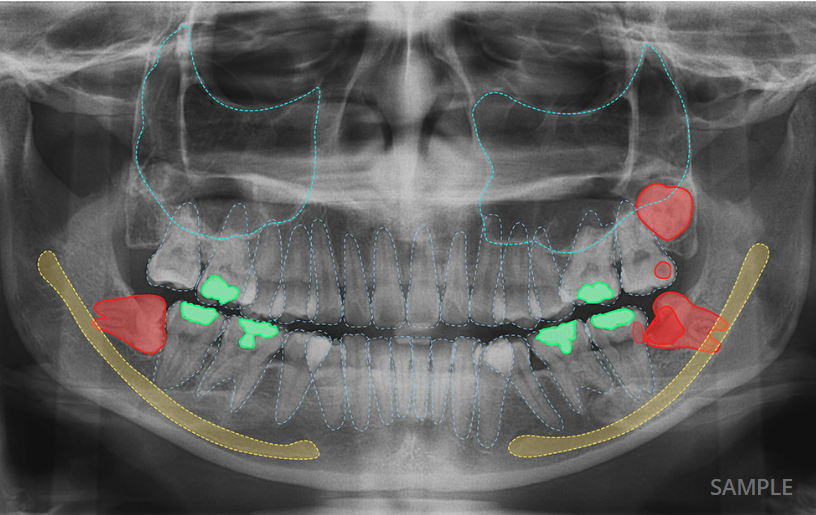

AI X-ray Detection & Automated Dental Charting

Ever wonder what your dental x-ray really shows? With our AI technology, you can now see it more clearly than ever.

The AI analyses your x-ray images within seconds and highlights areas that may need attention, such as tooth decay, impacted tooth, bone loss and etc. These are shown directly on your x-ray image, helping you understand what is going on at a glance.

The system also automatically updates your dental chart, which is part of your dental records, saving time and ensuring every detail is properly recorded.

Benefits:

- Clear, colour-marked visualisation on your x-ray

- Faster and more consistent record-keeping

- Better understanding of your oral health